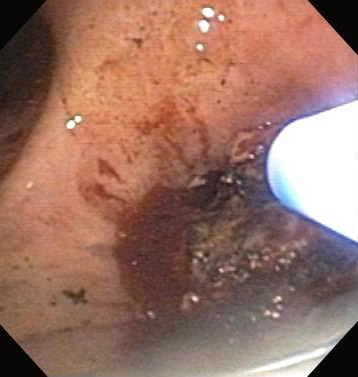

It induces less mucosal trauma and subsequent granulation tissue formation than does rigid dilation. Balloon tracheoplasty and bronchoplasty can be used in malignant and non-malignant CAO, stenoses following surgical resections and lung transplantation, and in post-intubation tracheal stenosis. BBP results in an immediate improvement in extrinsic and intrinsic malignant CAO in up to 79% of patients and is useful in airway dilation prior to stenting. As its effects are not long-lasting, BBP dilation is usually followed by other therapies such as laser resection, radiotherapy, or stenting. Complications include stenosis recurrence, pain, mediastinitis, and bleeding, as well as airway tearing or rupture with subsequent pneumothorax or pneumomediastinum.[Figure caption and citation for the preceding image starts]: Post-lung transplant anastomotic bronchial stenosisFrom the collections of Jose Fernando Santacruz MD, FCCP, DAABIP and Erik Folch MD, MSc; used with permission [Citation ends].

[Figure caption and citation for the preceding image starts]: Post-lung transplant anastomotic bronchial stenosis: balloon bronchoplastyFrom the collections of Jose Fernando Santacruz MD, FCCP, DAABIP and Erik Folch MD, MSc; used with permission [Citation ends].